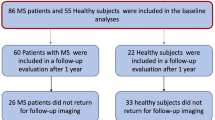

In this cross-sectional study, from February 2016 to January 2020, we prospectively enrolled MS patients diagnosed according to the 2010-McDonald criteria [16], along with age- and sex-comparable healthy controls (HC). Inclusion and exclusion criteria are shown in Fig. 1.

In total, 117 MS patients (85 relapsing-remitting, 22 secondary-progressive, 10 primary-progressive; 40.6 ± 11.9 years; F/M = 85/32) were included in the study, along with 53 HC (41.3 ± 11.6 years; F/M = 33/20) (Fig. 1). The mean disease duration (DD) for MS patients was 12.7 years (SD: 8.3), with a median EDSS score of 3.0 (interquartile range: 2.0–5.25) and a mean T2-LL of 6.2 ml (SD: 10.7). A total of 110 patients (94.0%) were under immunomodulatory treatment (32% with first-line therapies: interferon, glatiramer acetate, dimethyl fumarate, teriflunomide; 62% with second-line therapies: fingolimod, siponimod, natalizumab, alemtuzumab, ocrelizumab, cladribine) at the time of the MRI.